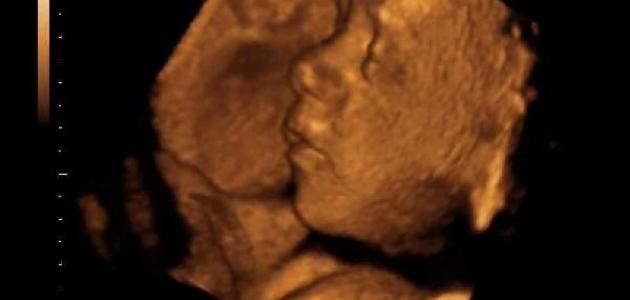

- أطفال الأنابيب: (بالإنجليزية: In vitro fertilization)، تُمثل إحدى تقنيات المساعدة على الإنجاب، ويتمثل هذا الإجراء باتّباع خطوات مُعينة لتُسفر في النهاية عن إخصاب حيوان منوي لبويضة مخصبة خارج الرحم ثمّ نقل البويضة المخصبة إلى رحم المرأة على أمل انغراسه فيه ونموّه، وفي الحقيقة يضع الأطباء المختصون عدّة بويضات مخصبة في الرحم؛ لزيادة احتمالية ثبات الجنين في الرحم، وهذا بحدّ ذاته يُساهم في زيادة احتمالية الحمل بتوأم.